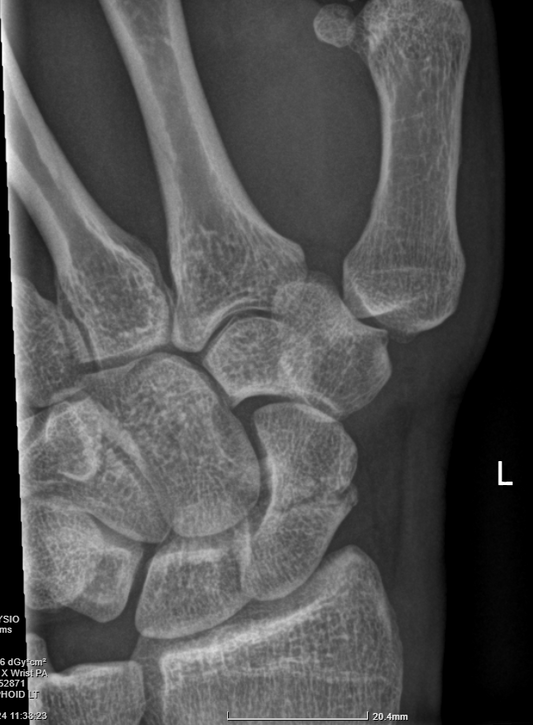

How are scaphoid fractures diagnosed?

Scaphoid fractures are diagnosed based on clinical examination findings, and imaging. It is usually tender to push over the anatomic snuffbox on the thumb side of the back of the...